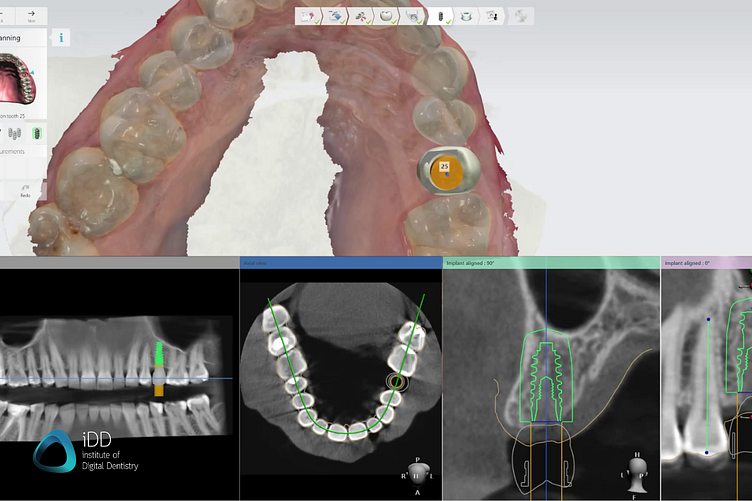

To create a surgical guide, precise digital models of the patient's oral structures are needed, both surface and internal. Intraoral scanning enables the capture of accurate digital models of the patient's dentition and surrounding tissues. Cone beam computed tomography (CBCT), provides comprehensive 3D models of the patient's bone structures. This data will be important for assessing the ideal implant position with regard to the patient’s anatomy.

Patients’ CT scans with intraoral scans should provide enough information for safe and functional implant placement. Software: 3Shape Implant Studio.

For a restorative-driven workflow, a digital tooth mock-up is used to help find the most aesthetic and functional implant position. CBCT data help you account for bone density, sinus, or inferior alveolar nerve.